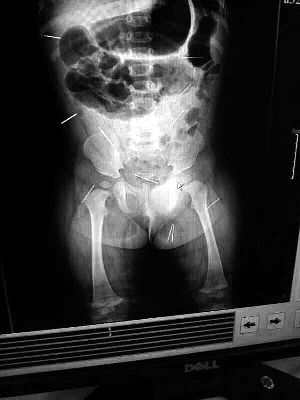

山東聊城11個(gè)月女?huà)胼孑妫ɑ┮伤票蝗艘?2根鋼針插滿臀部、腹腔等部位,昨天在兒童醫(yī)院會(huì)診后,醫(yī)生稱3根針靠近胸腔最危險(xiǎn),首批先行取出,預(yù)計(jì)將在下周二手術(shù)。孩子父母稱孩子一直由家人照顧,自家與他人并無(wú)冤怨。山東警方表示正在偵破中,不便透露案情。

“要不是當(dāng)初那幾個(gè)紅點(diǎn),可能到現(xiàn)在我們還不知道孩子身體里有鋼針!”昨天,在兒童醫(yī)院住院處,萱萱爸爸范先生稱,日前原本很愛(ài)笑的萱萱突然變得有些焦躁,一抱起來(lái)就哭,孩子母親偶然間在萱萱屁股上發(fā)現(xiàn)了幾個(gè)小紅點(diǎn)兒,原以為是蚊蟲(chóng)叮咬,就醫(yī)結(jié)果卻讓人不寒而栗?!搬t(yī)院拍出的片子上,萱萱的體內(nèi)有12根鋼針,插滿臀部、腹腔、骨盆等各個(gè)部位?!狈断壬榻B,因?yàn)殇撫樢焉钊塍w內(nèi),要是孩子不哭鬧,他們很難發(fā)現(xiàn)。

北京晨報(bào)記者了解到,目前體內(nèi)的12根鋼針多分布在孩子的臀部,一根在腹部,其余3根在胸腔附近,其中一根很接近心臟?!耙?yàn)楹⒆犹。t(yī)生們害怕取針的時(shí)候?qū)λ斐蓚?,在胸腔附近?針可能會(huì)威脅她的生命”。